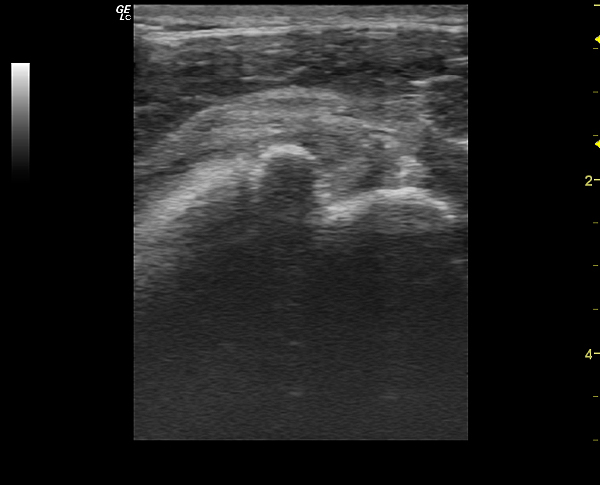

Мужчина 48 лет, нес сварочный аппарат весом под 30 кг, споткнулся и упал на плече.

После 2 недель хождений по разным врачам, различного противовоспалительного лечения, пришел на УЗИ плечевого сустава.

И вот такая уз-картина предстала перед моим взором.

На представленных сонограммах сканирована головка плечевой кости с ротаторной манжетой.